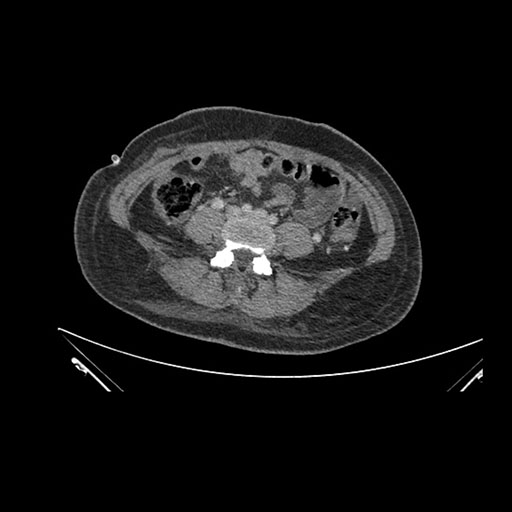

Axial Venous